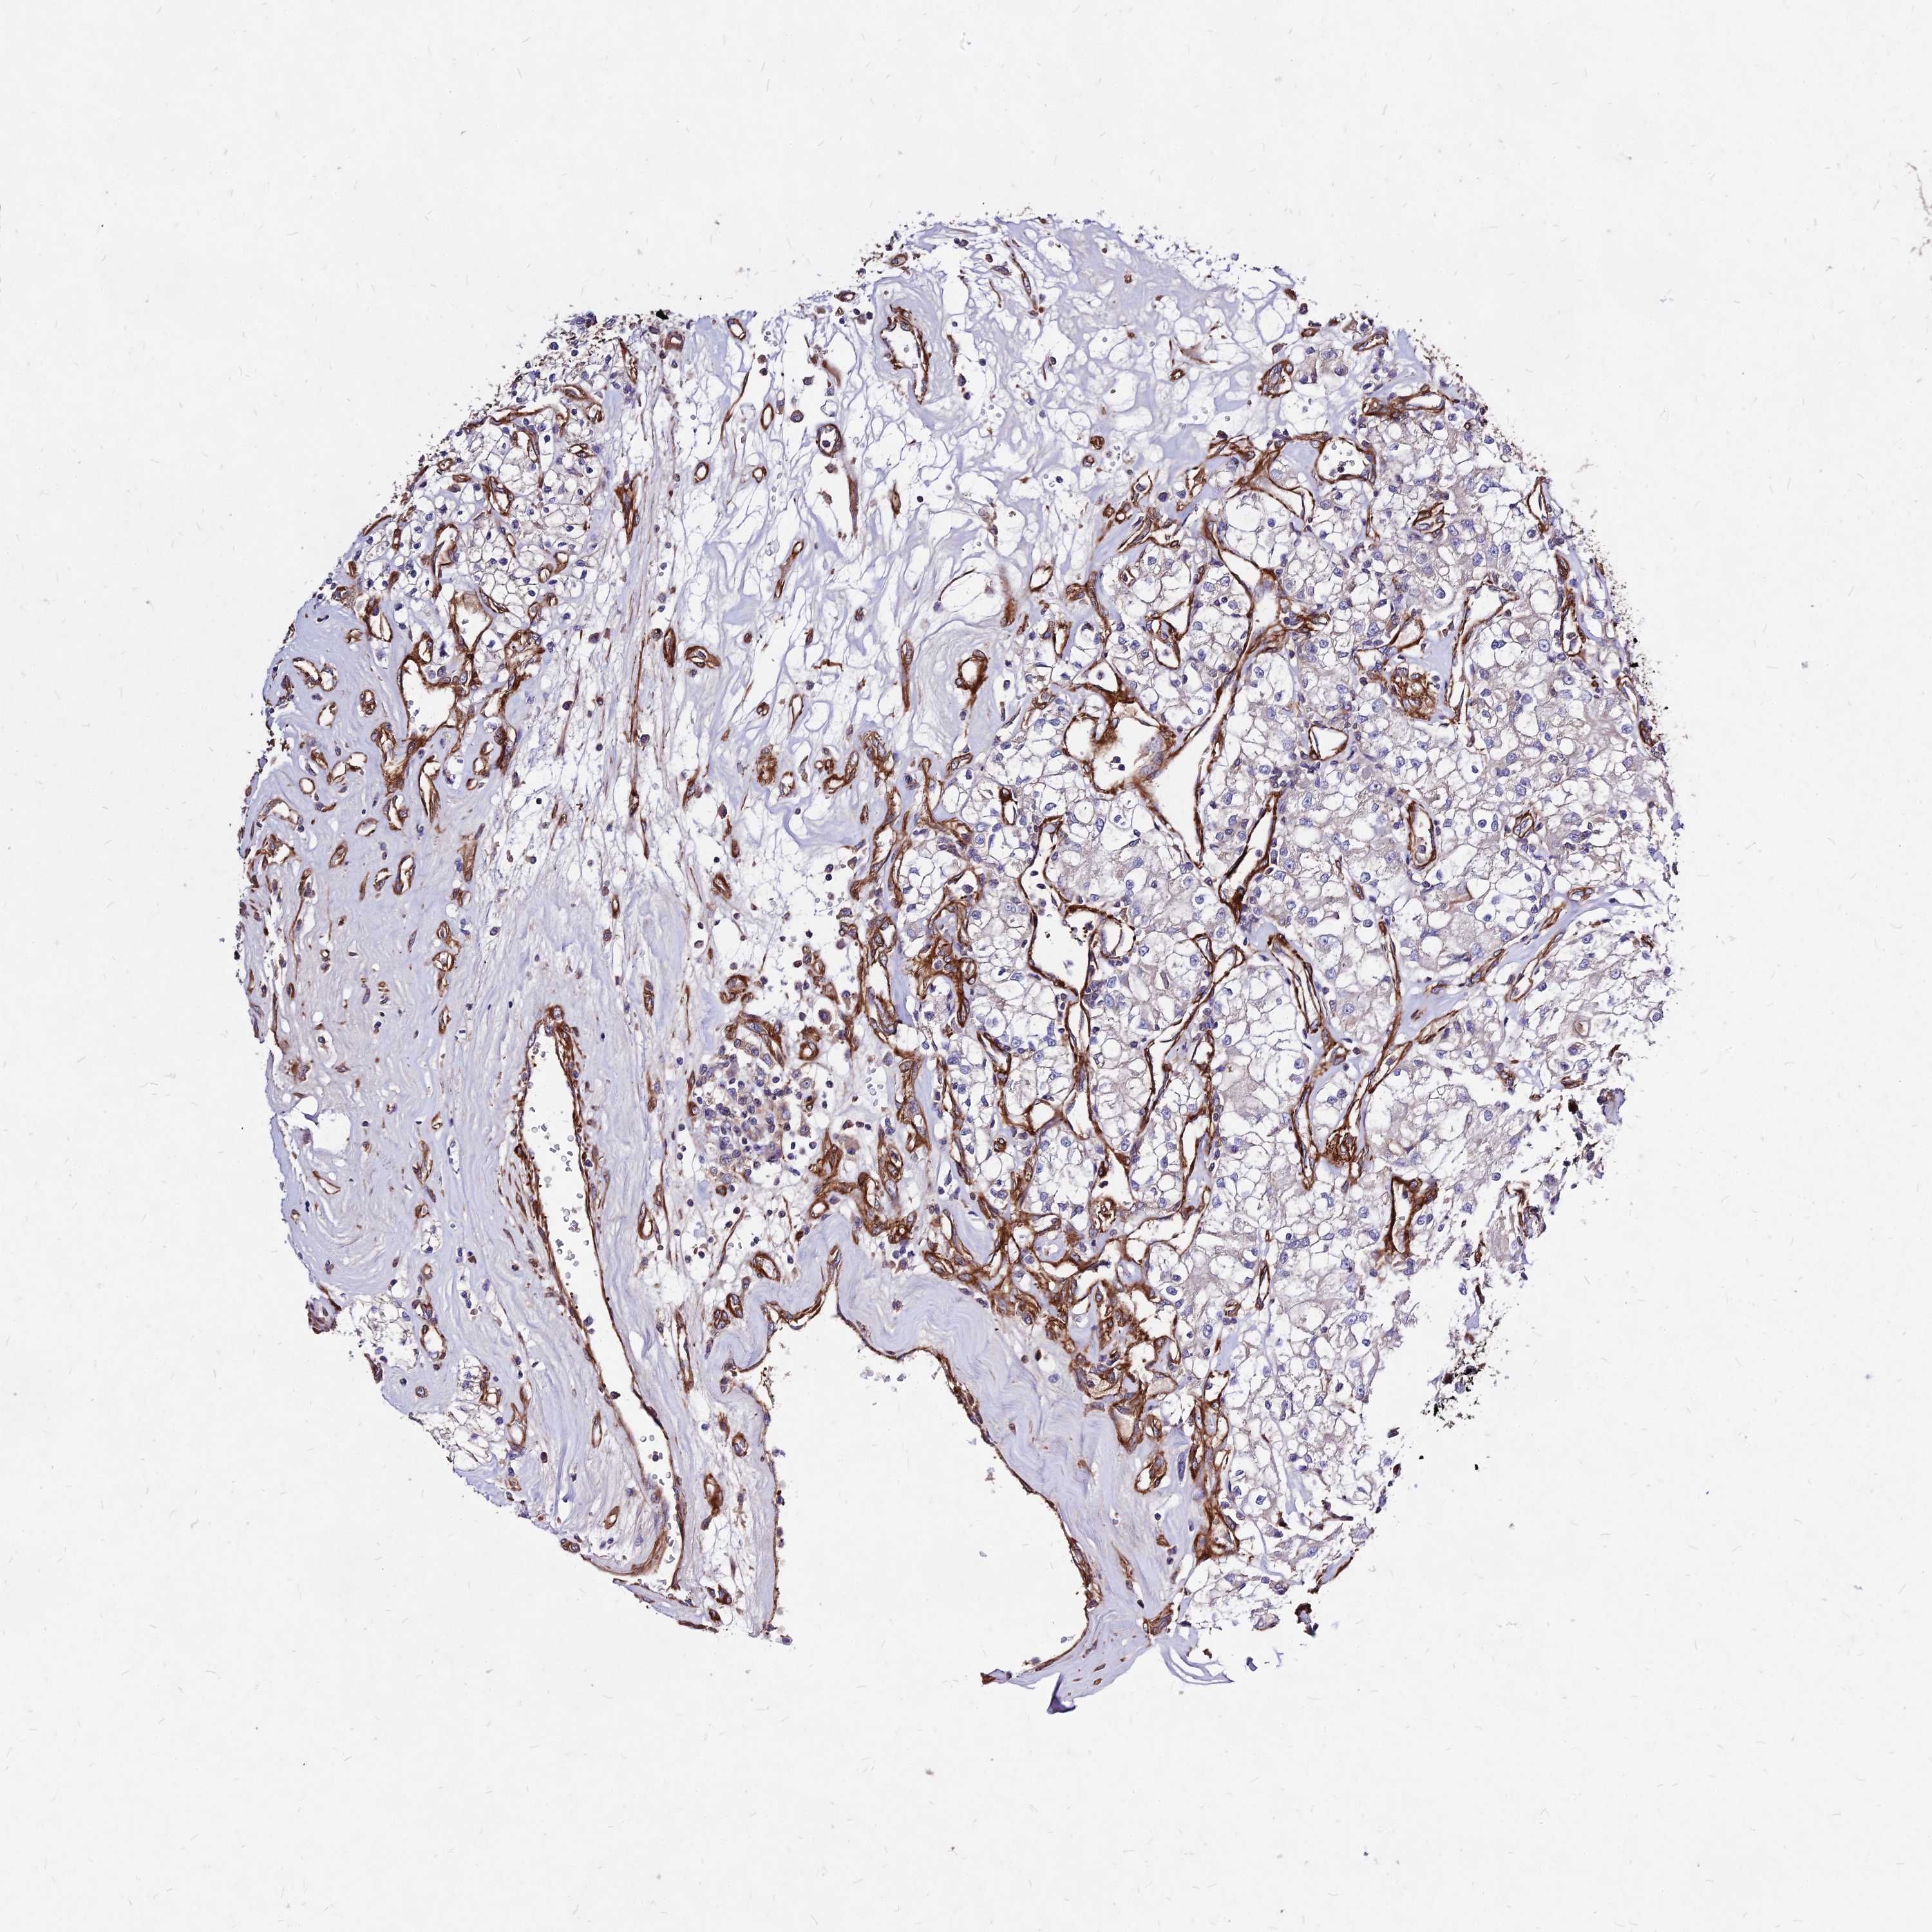

CANCER RENAL CANCER Show tissue menu

KICH TCGA KIRC TCGA KIRC VALIDATION KIRP TCGA PROTEIN RCC CPTAC PROTEIN EXPRESSION